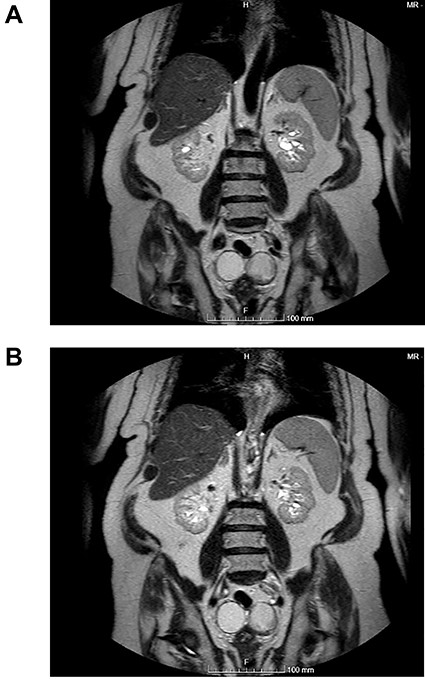

(A and B) Coronal images of MR showing bilateral ovarian teratoma.

The authors report the case of an asymptomatic 76-year-old female patient, referred to our Gynaecologic Clinic, due to suspicious adnexal lesions on a pelvic ultrasound (US). Menopause occurred at age 53. She had no history of abnormal uterine haemorrhage. Her menstrual cycles had been regular. She had had three gestations: two late abortions and one normal delivery, after which she breastfed. At our clinic, upon examination, vulva, vagina and cervix had no apparent lesions. The vaginal US revealed a right adnexal avascular cystic lesion of 65 mm, a left adnexal hyperechogenic cystic lesion of 60 mm, a normal sized uterus, a diffusely heterogeneous myometrium, an endometrial thickness of 8 mm and heterogenous intracavitary liquid. Her risk of ovarian malignancy assessment (ROMA) score was 28.1%, for a cut-off of 25.3%. Cancer antigen (CA) 125 and Human epididymis protein 4 (HE4) were 25.9 and 98.2, respectively. Lactate dehydrogenase (LDH), alpha fetoprotein (AFP) and beta human chorionic gonadotropin (bHCG) were normal. She subsequently had a magnetic resonance (MR) done (Fig. 1), which suggested bilateral ovarian teratoma. She also had an upper digestive endoscopy and a hysteroscopy that were normal and a computed tomography (CT) done (Figs 2–4) that showed: in the right adnexal region, a solid well-demarcated tumoural mass of 55 mm, with predominantly fat density, peripherical calcifications and a central hyperdense image (similar to a tooth), suggestive of a teratoma; in the left adnexal region, a predominantly cystic bilobated tumoural mass of 65 mm, with peripherical calcifications and an area of fat density, also suggestive of teratoma; and no additional disease. This case was presented at our Multidisciplinary Tumour Board, where surgery was proposed. Thus, she underwent exploratory laparotomy, peritoneal washing, total hysterectomy and bilateral adnexectomy, which ran uneventfully. Intra-operative frozen section excluded ovarian malignancy. She had an uneventful recovery and was discharged home on the third post-operative day. The pathological report revealed bilateral mature cystic teratoma with representation of the three germinative layers and thyroid parenchymal tissue (struma ovarii) (Fig. 5). Both ovaries were atrophic and had a cavitated lesion covered by respiratory epithelium with hyaline cartilaginous, adipose, smooth muscular and mucosa-associated lymphoid tissues (positivity for CD3 and CD20), seromucinous glands and thyroid follicles (homogenous positivity for thyroglobulin). Thyroid follicles were well differentiated, without features of malignancy. Fallopian tubes were normal. There were also uterine leiomyomas and a mucosal endocervical polyp. She was euthyroid and had a thyroid US done, which was normal. Follow-up at first post-operative month, remaining asymptomatic.